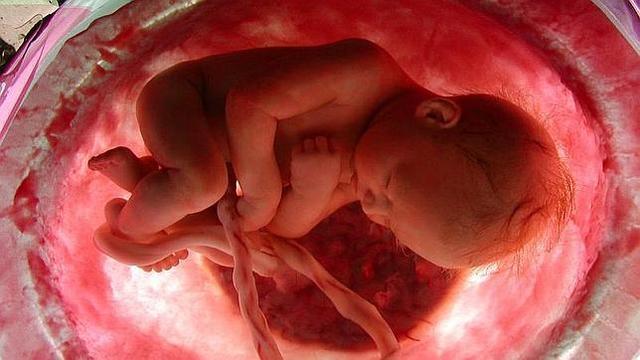

Las medidas aproximadas del feto a estas alturas del embarazo son de 36 cm de longitud y casi 1 kg de peso. A partir de ahora será habitual sentir el hipo del bebé en forma de pequeños espasmos muy diferentes a las patadas o movimientos típicos. Éste no suele durar mucho y tampoco es molesto para el feto. No se podrá oír, pues los pulmones del bebé aún no poseen aire.

En estos días empieza a notarse la presión que ejerce el crecimiento del bebé sobre los órganos internos de la madre, está prácticamente formado. Sin embargo, los pulmones aún no han finalizado su evolución, ya que son los órganos que lo hacen con mayor lentitud.

El feto, que ya tiene unas medidas mucho más proporcionadas, se moverá con mucho vigor y sus movimiento se podrán notar incluso sobre la propia piel de la madre.